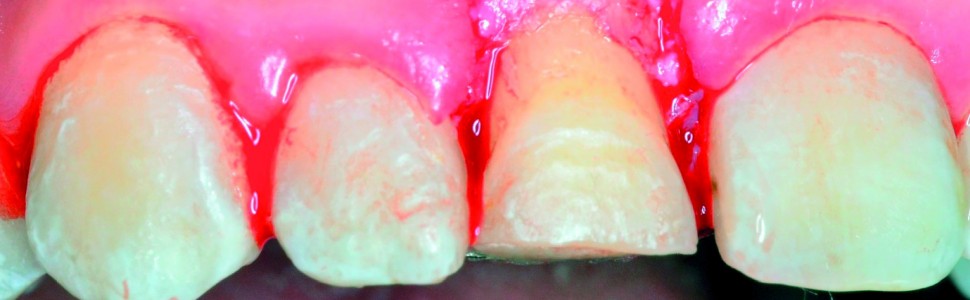

Celem pracy było przedstawienie wielospecjalistycznego leczenia skośnego poddziąsłowego złamania zęba siecznego przyśrodkowego u nastoletniej dziewczynki. Ząb po leczeniu endodontycznym poddano ekstruzji ortodontycznej, po której zakończeniu wykonano wydłużenie korony klinicznej i pośrednią estetyczną odbudowę kompozytową, uzyskując zadowalający efekt estetyczny i funkcjonalny. U współpracujących dzieci złożone złamania koronowo-korzeniowe zębów stałych można skutecznie leczyć, wykorzystując możliwości terapii wielospecjalistycznej.

The aim of this paper was to present a multidisciplinary treatment approach to central incisor subgingival oblique fracture in a teenage girl. After endodontic treatment the tooth was subjected to orthodontic extrusion, and then the clinical crown lengthening and intermediate aesthetic reconstruction were applied. The achieved aesthetic and functional result was satisfactory. Complicated root canal fractures can be effectively treated in co-operating children utilizing an interdisciplinary approach.